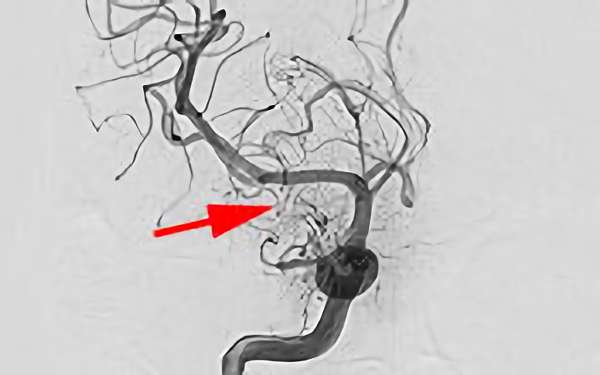

'25年4月

くも膜下出血

右内頚動脈脳動脈瘤破裂

50代

救急外来

No.1544 手術前

No.1544 手術中

No.1544 手術後